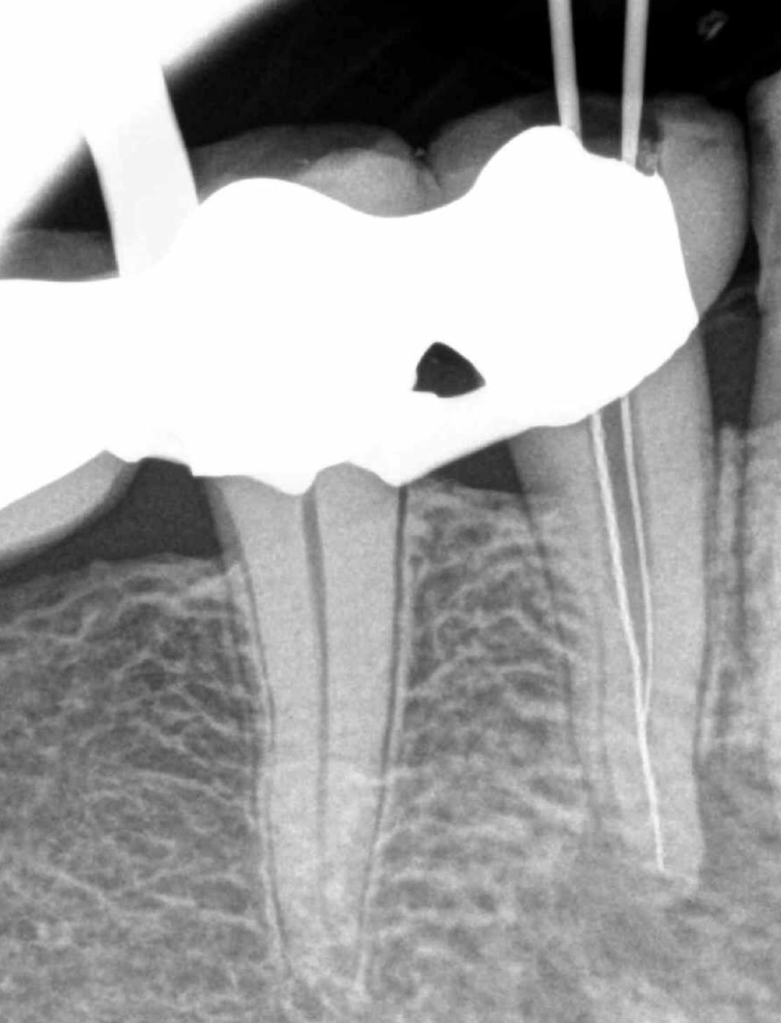

Molar inferior, conducto CM